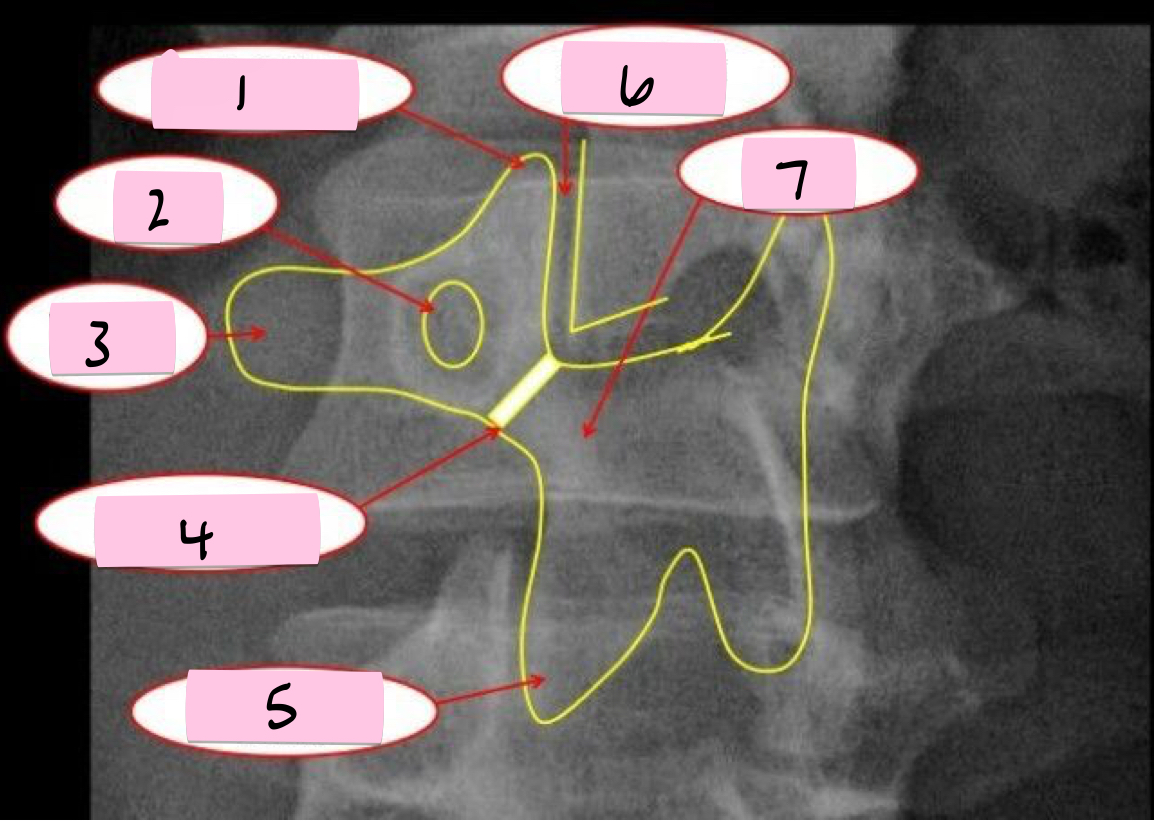

What is 1 pointing to?

Superior articular process

What is 2 pointing to?

Zygapophyseal joint

What is 3 pointing to?

Transverse process

What is 4 pointing to?

Pars interarticularis

What is 5 pointing to?

Inferior articular process

What is 6 pointing to?

Pedicle

What is 7 pointing to?

Scotty dog